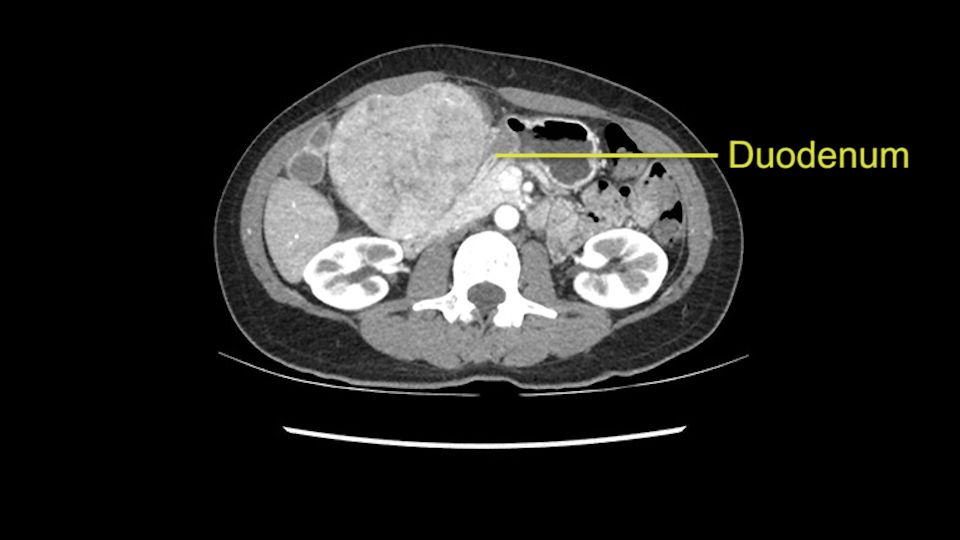

When you see the axial sections of the scan, you find it's a largely exophytic mass and its well-encapsulated. So this is typically true of a well-differentiated hepatocellular carcinoma. If you look at this, this is the gallbladder which is being displaced to the right and the mass is in the Sg4 of the liver, exophytic, projecting down. As it is coming down, it is also displacing the duodenum and the head of the pancreas which is being pushed towards the left and it's going right up to the cava, the start of the anterior surface of the cava. Obviously getting a lot of collaterals and vascularity from all the vessels around but one has to be very careful in evaluation of the main portal pedicle in this particular case and of course arterial inflow to the Sg4 and of course the left lobe of the liver.

Now coming to the duodenum, we can see that the stomach is coming down, and as it comes down to the head of the pancreas, it’s compressed by the mass which is distorting the duodenum completely. Is there invasion of the duodenum or not? When you see a little above, there is a very well nicely capsulated tumor so my impression is that it is only displacing the duodenum, may not be invading the duodenum. But however intraoperatively one has to be careful in dissecting the duodenum from the tumor.

So in planning for this operation, as I look at the scans, I first visualize the arterial phase and I can see that there’s are a lot of big feeding arteries to this large tumor. Likely all the right side vessels feeding the right side of the liver: right hepatic artery and likely the Segment 4 artery are spared from the tumor. It’s likely the left hepatic artery is ramificating and giving feeding arteries to this tumor. It certainly looks like a large mass that its compressing other structures like the cava, the pancreas, the stomach; but I think there’s a plane and we can see that better in the venous phase. There’s a plane of separation between the gallbladder, the pancreas, the cava, that this tumor is abrupting but likely not invading. Usually, these masses actually don’t invade at that level and basically are pushing the tissues and once you open, you’re able to separate the tumor. Sometimes there’s some adhesions but you can actually separate and there’s usually no invasion.